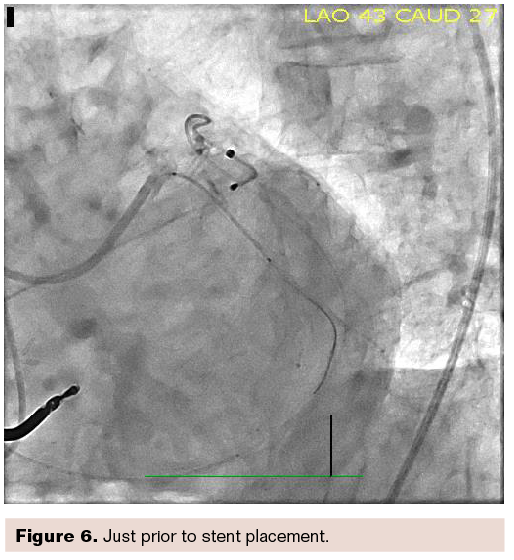

Note also the very clear image in Figure 6, which was just prior to stent placement.